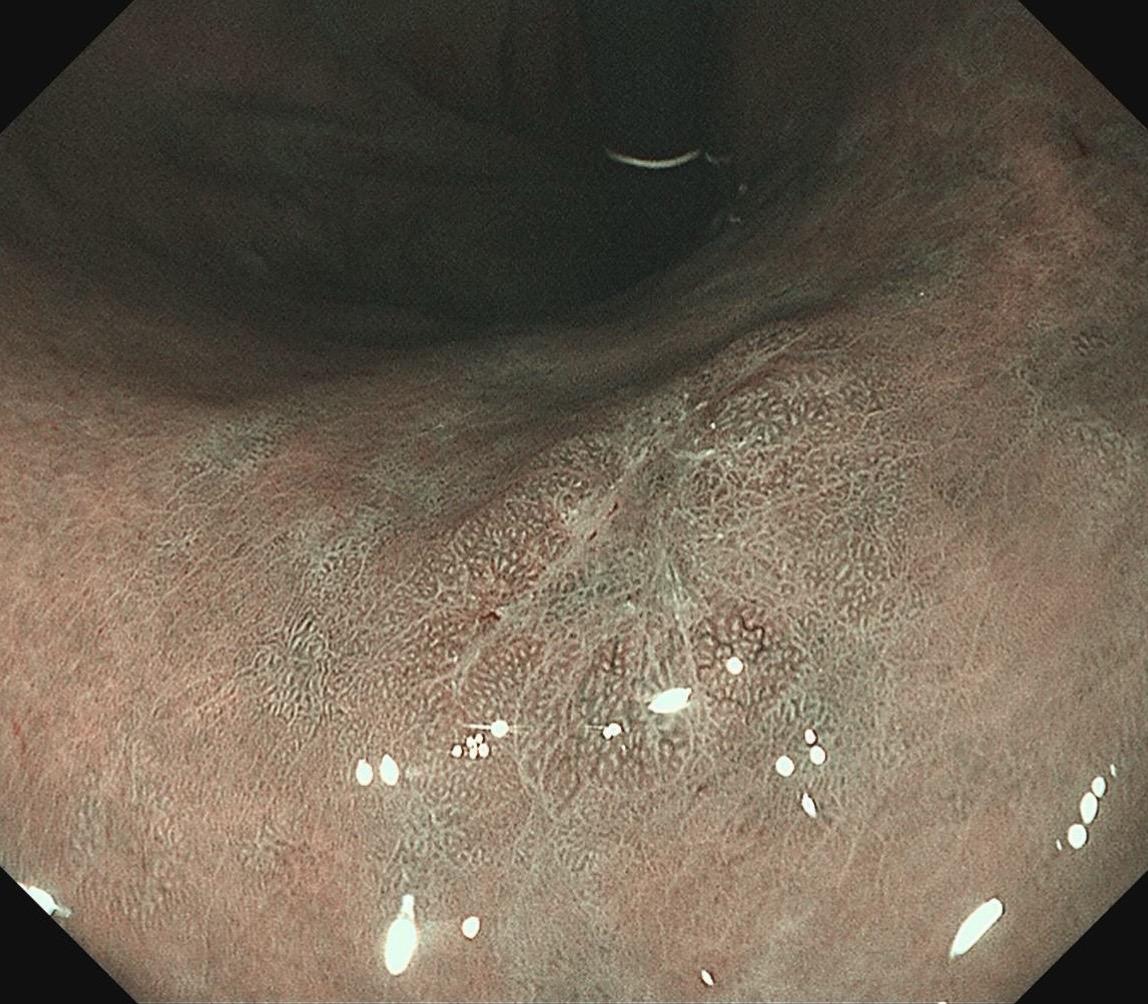

女,57岁,胃角。同事熟人,萎缩背景,色调淡黄,中央浅凹陷,腺管小而密集。